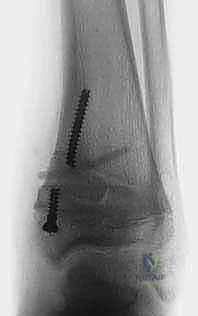

الخطوة الرابعة: تثبيت الشريحة (8-Plate)

بمهارة فائقة، يقوم الدكتور هطيف بوضع الشريحة المعدنية المصنوعة من التيتانيوم الطبي النقي فوق مركز النمو. يتم تثبيت الشريحة باستخدام مسمارين صغيرين؛ أحدهما فوق خط النمو والآخر تحته. هذه المسامير لا تخترق مركز النمو نفسه، مما يضمن عدم تدميره.

- الأشهر من 1 إلى 6: هذه هي مرحلة "السحر الطبي". خلال هذه الأشهر، ومع نمو الطفل، يبدأ الانحراف بالتلاشي تدريجياً. تتم جدولة زيارات دورية لعيادة الدكتور هطيف لإجراء أشعة سينية ومراقبة تقدم التصحيح.

- إزالة الشريحة: بمجرد أن يستقيم الكاحل ويصل إلى الزاوية الطبيعية المثالية (غالباً بعد 6 إلى 12 شهراً)، يتم إجراء عملية جراحية صغرى وسريعة جداً لإزالة الشريحة والمسامير، ليُترك الطفل بقدم سليمة ومفصل طبيعي تماماً.